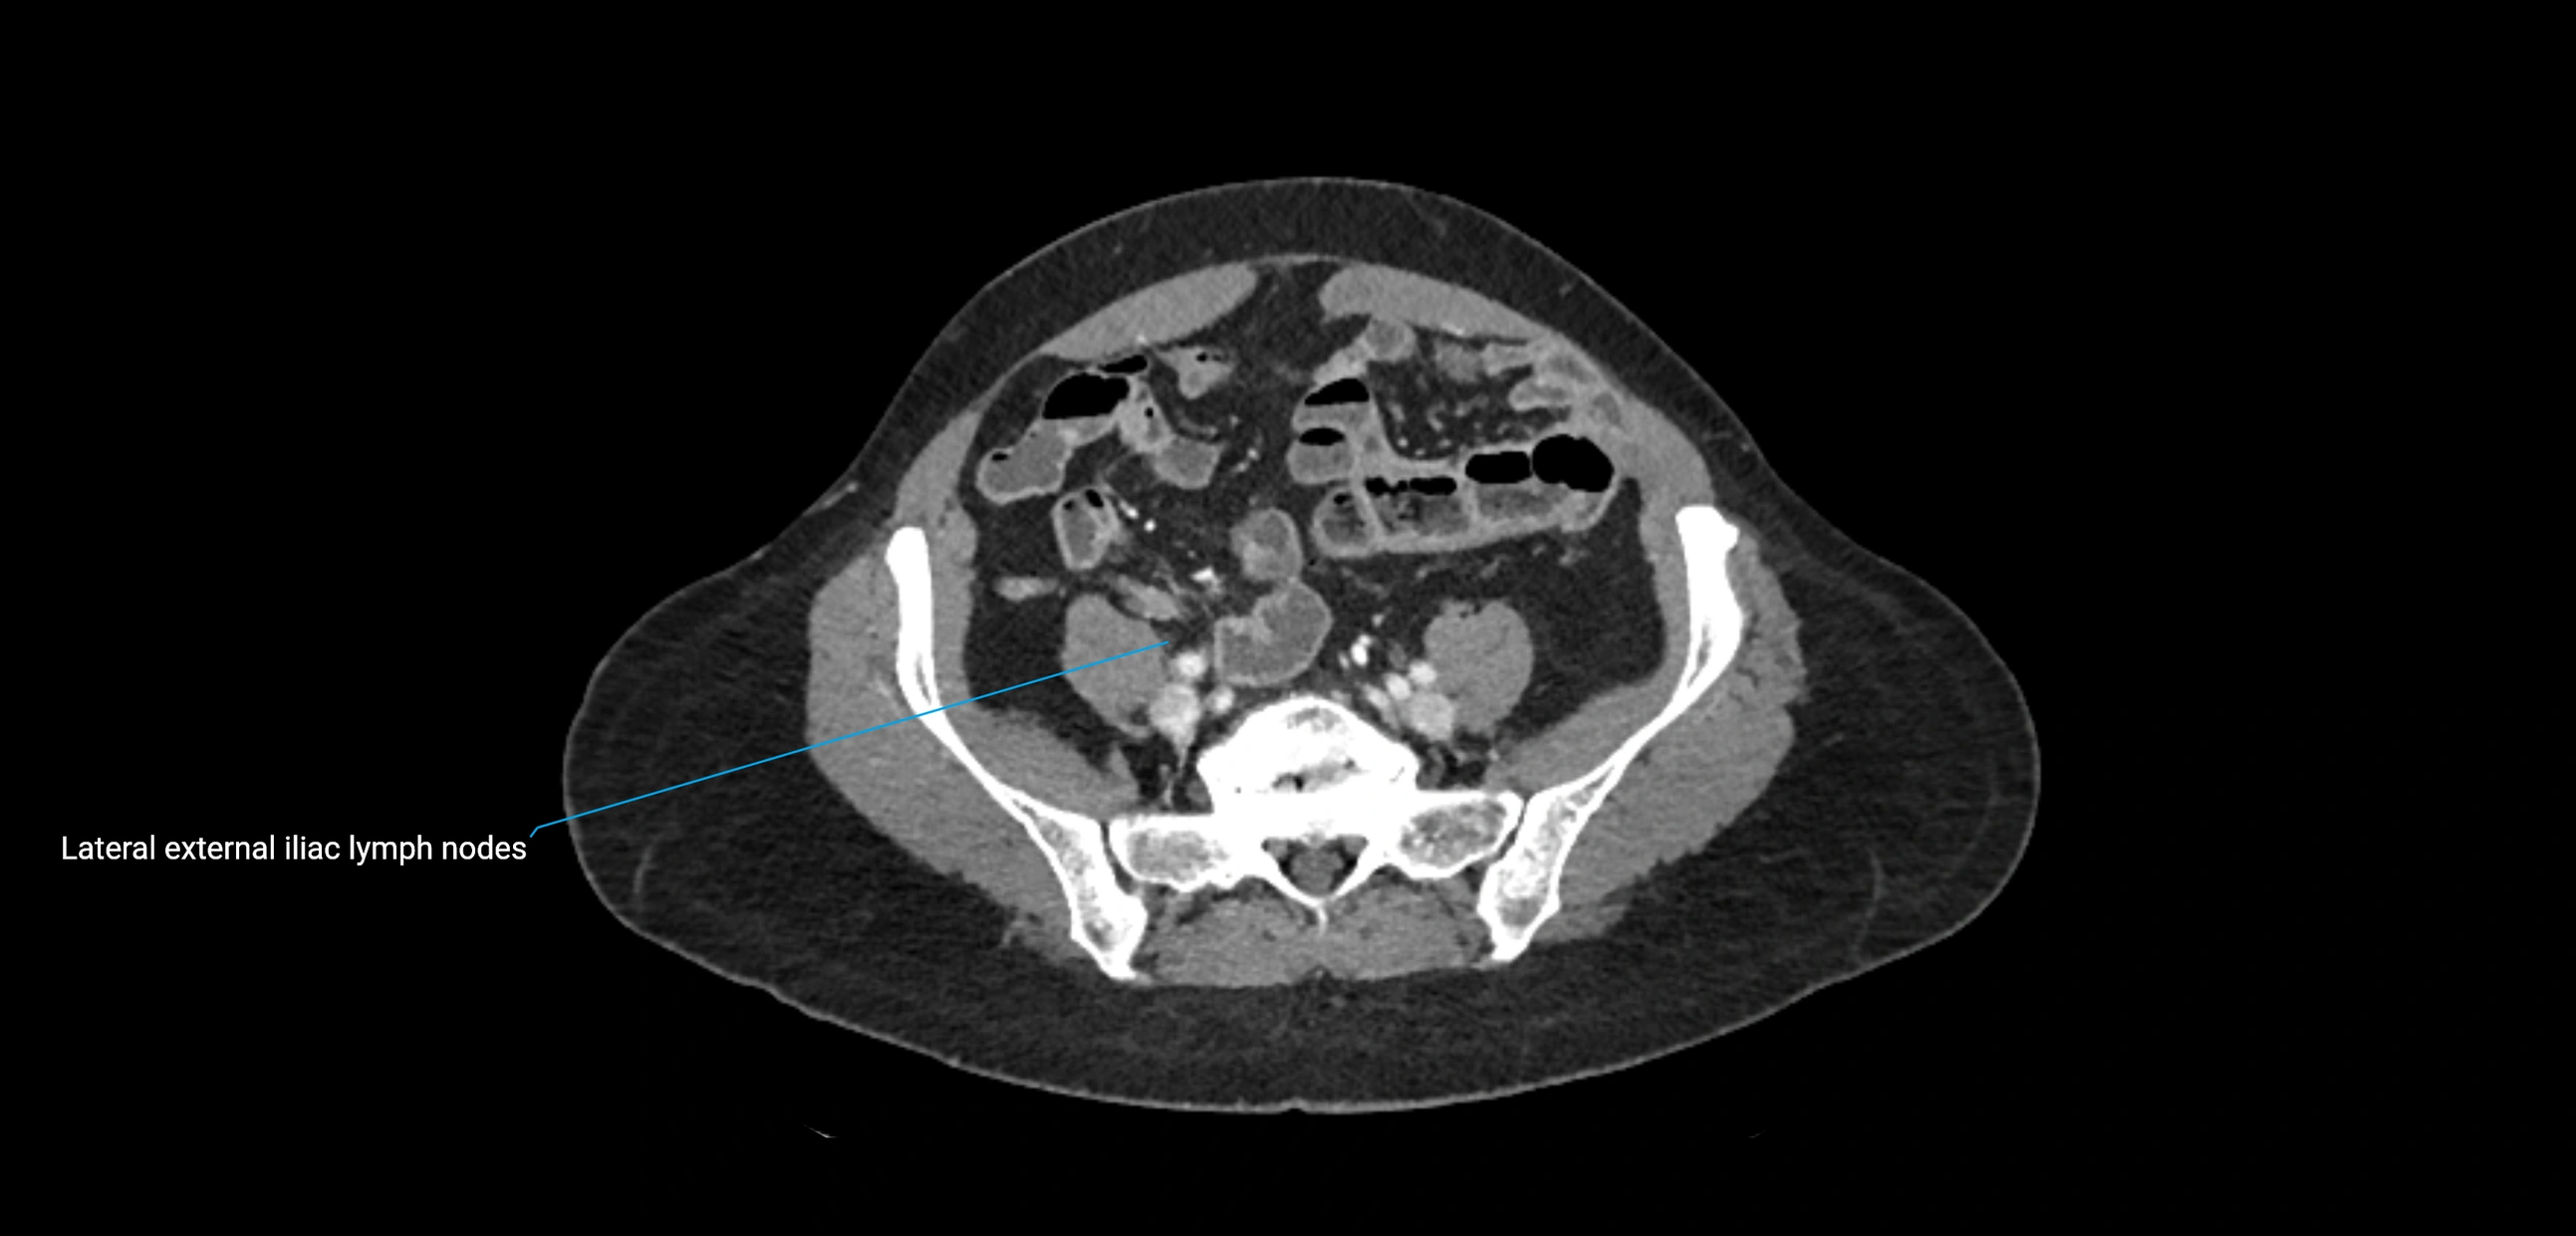

CT Appearance

CT Pre-Contrast:

• Nodes appear as soft-tissue density nodules adjacent to the aorta and IVC

• Calcification may be seen in chronic infections (e.g., tuberculosis)

CT Post-Contrast:

• Normal nodes enhance homogeneously

• Malignant nodes may show heterogeneous enhancement, central necrosis, or conglomerate formation

• Size >1 cm short axis is suspicious, though morphology and distribution are equally important